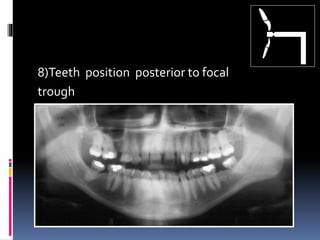

8)Teeth position posterior to focal

trough